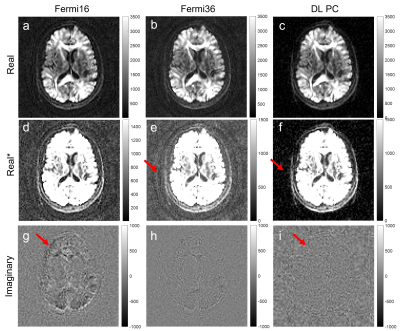

DL-based phase correction also achieved similar performance in extreme low SNR images. The single NEX image at b=8000 is very noisy. It is challenging to distinguish high-frequency background phase from noise using conventional denoising method. With DL-based phase correction, the imaginary channels for both single and multi-NEX images are mainly dominated by noise and there is no signal left in the imaginary channel after phase correction. This indicated that DL-based method achieved robust phase correction at extreme low SNR.

Figure 3. Complex averaging using DL-based phase correction with b=8000 brain images. (a-b) are the real images; (c-d) are the imaginary images. DL-based phase correction showed robust phase correction without noticeable signal loss at extreme low SNR.